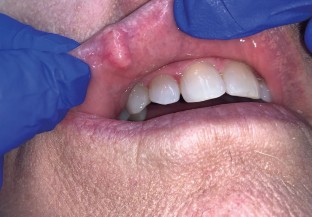

The aim of this review was to characterise the clinical features of basal cell carcinomas (BCCs) occurring on the lips. A review of the literature was performed using PubMed to identify reports of BCCs of the lips. Additionally, a retrospective search of the archives of our diagnostic oral pathology service was performed for BCCs diagnosed between 2000-2023. There were 27 BCCs of the lips identified in the literature review. These tumours typically presented clinically as bleeding, eroded, crusted, ulcerated and/or centrally depressed nodules. Treatment included surgical excision, Mohs micrographic surgery, wedge resection and radiation. None recurred or metastasised. Ten additional cases of BCC of the lips were retrieved from our archives. Six of these BCCs exhibited a classic clinical presentation, being described as red, white, crusted, bleeding, scabbing, eroded and/or ulcerated lesions. Four tumours were considered non-classic, presenting as yellow nodules. To the best of our knowledge, this is the first report of BCCs on the lips presenting as yellow nodules. It is important for clinicians to be aware of this rare presentation of BCC in the oral and perioral region as it may mimic benign entities.

Basal cell carcinomas of the lips usually occur on the cutaneous surface but may rarely involve the mucosal portion of the lips.

Basal cell carcinomas of the lips are typically bleeding, crusted and/or ulcerated but may present as yellow nodules and mimic benign entities.